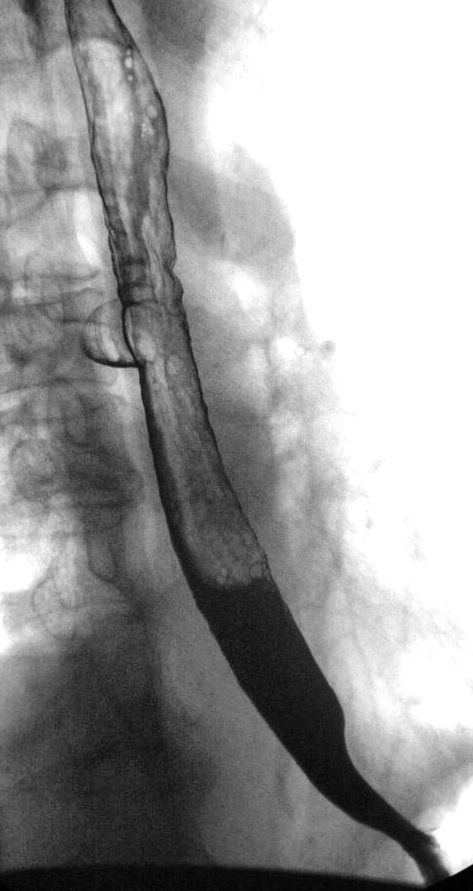

Пищевод.

дивертикулы пищевода

Изображение  Изображение

Естественно есть признаки дивертикулита- в 1ю очередь слабо выражено, но 3-х слойность за счет наличия слизи.

"выпячивание" стенки пищевода, указанное над диафрагмой вероятнее всего ГПОД, склдки желудочного типа.